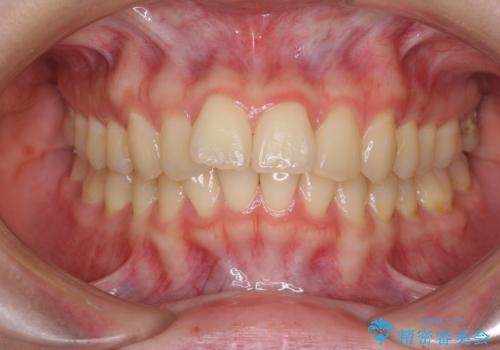

- 前歯2本が飛び出してることを気にして来院された患者様です。

全体的に黄ばんだ歯の色も気になるとのことで、マウスピース矯正により飛び出した前歯を治しつつ、ホームホワイトニングを併用して黄ばみを解消していくこととしました。

歯と歯の間を削ることで、飛び出した前歯が引っ込み、スッキリとした口元となりました。

歯の黄ばみも改善され、明るい歯並びとなりました。